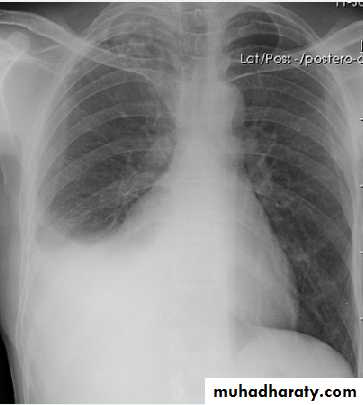

Left side massive pleural effusion with mediastinal

shift2-Ultrasonography is more accurate than plain chest radiography at determining the volume of pleural fluid. facilitates safe needle aspiration and guides pleural biopsy. may also distinguish pleural fluid from pleural thickening.